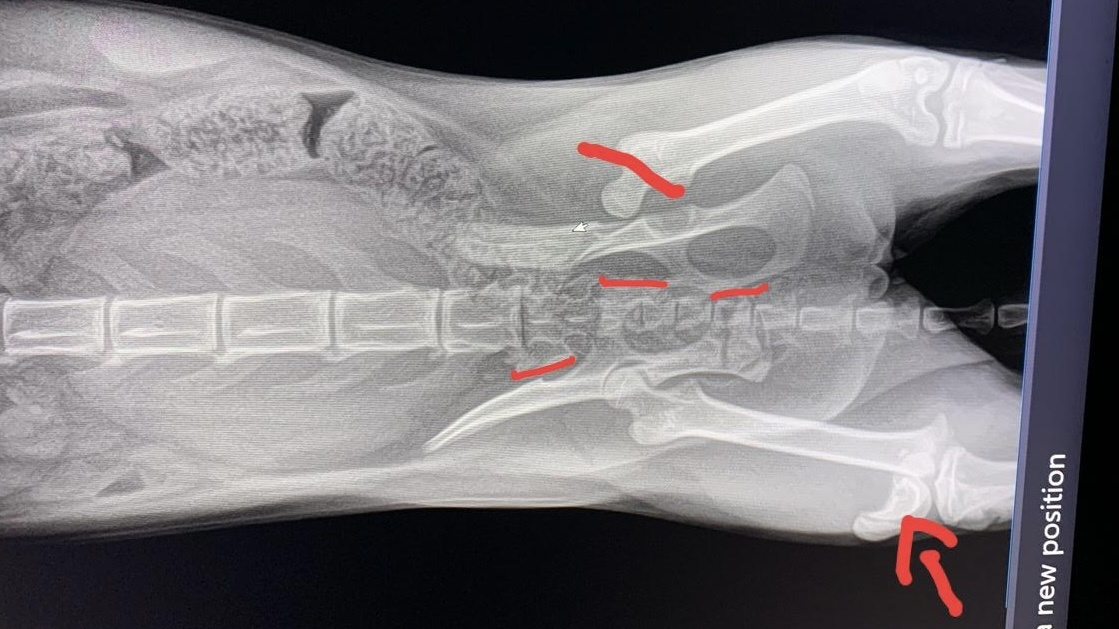

Очень ухоженная, красивая, нежная и ласковая кошечка. Сделали рентген... без комментариев...

Когда врач стал оперировать колено, он под наркозом сделал ещё один снимок и выяснилось, что у Юноны три пер'елома: бедро, колено и таз! Такое впечатление, что по ней проехалась машина! Вот до чего доводит самовыгул!